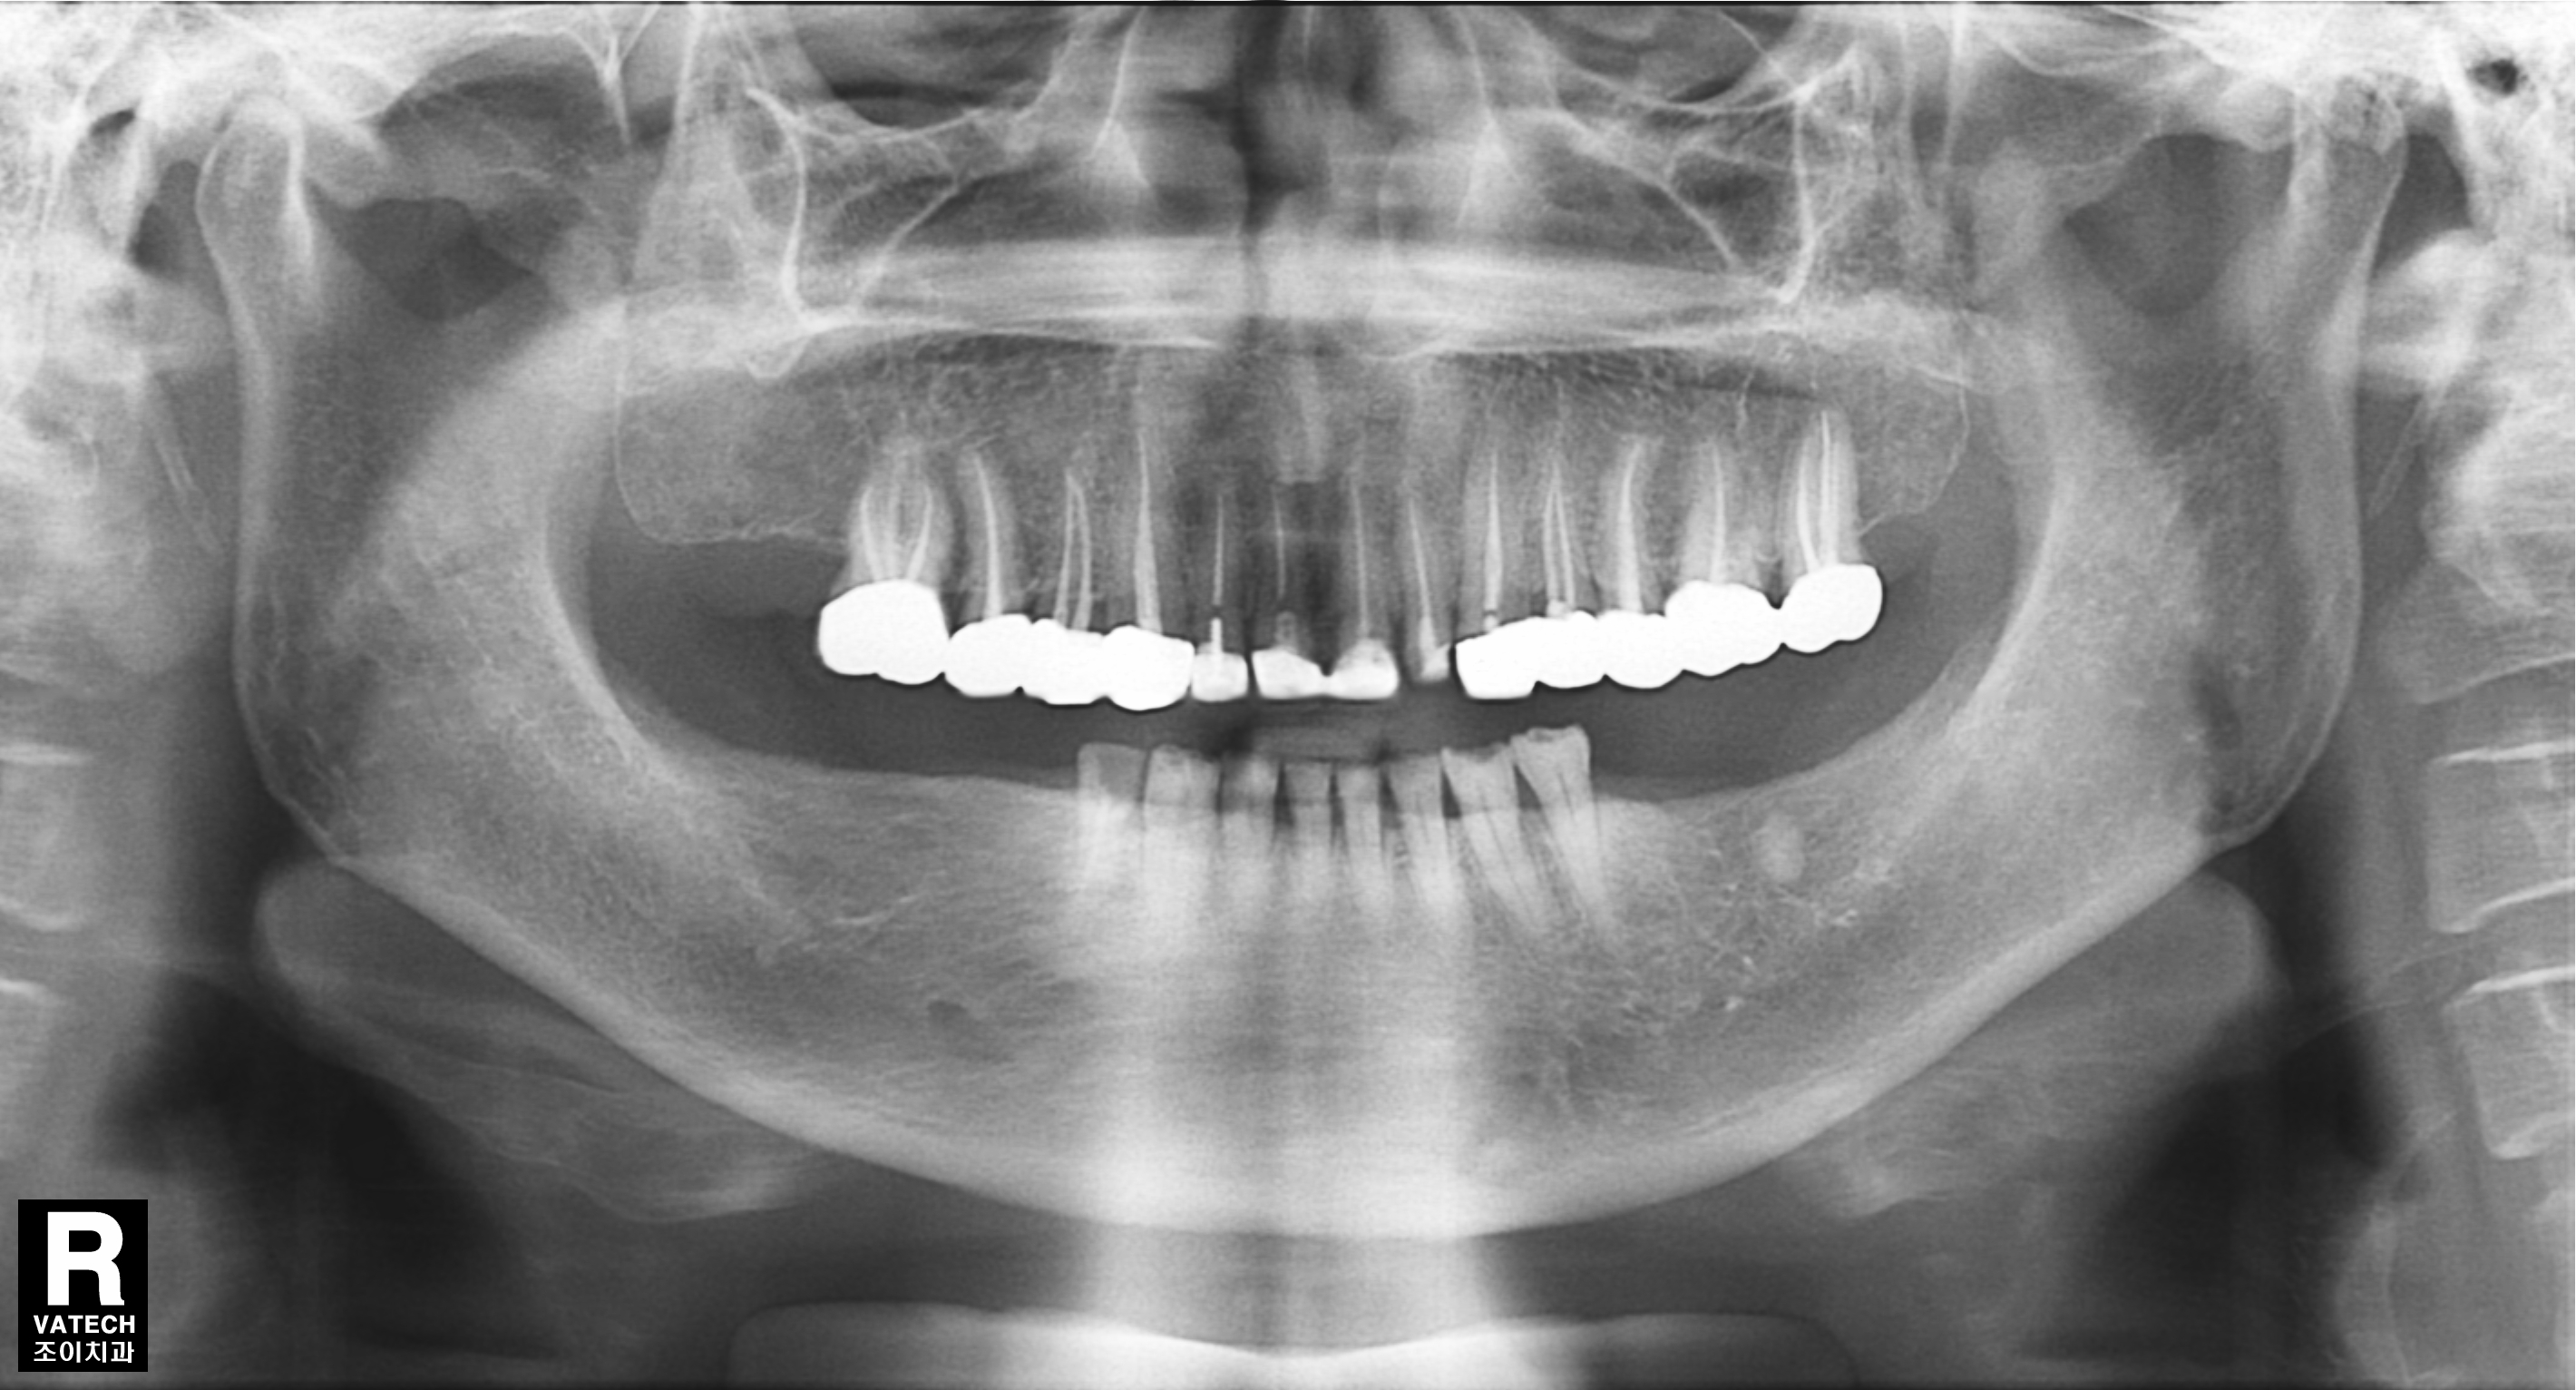

[임플란트] 제목 : 치아상실 후 임플란트

다수 치아의 상실 후 임플란트 치료